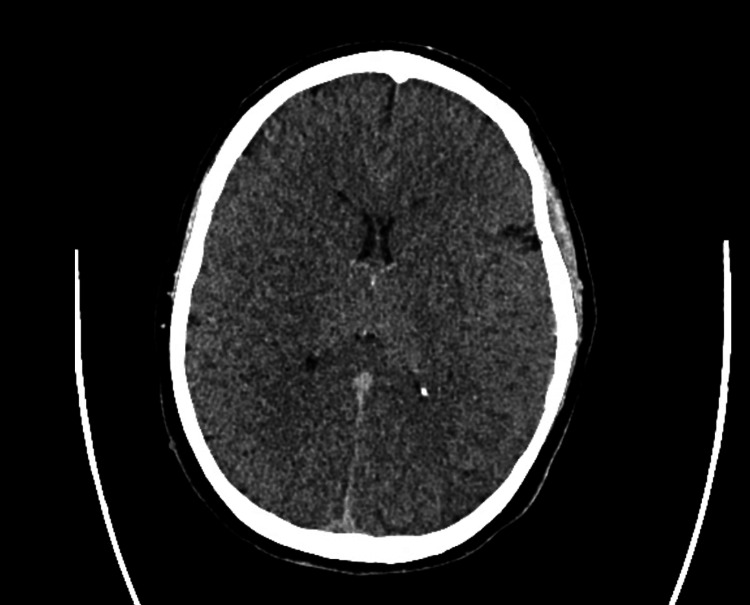

The patient was a 31-year-old female who arrived at the emergency department after being found unresponsive following an episode where she and a friend lost consciousness after using an unknown substance. The family denies any known hereditary diseases. Upon arrival, she required immediate intubation and cardiopulmonary resuscitation (CPR). Her initial ECG findings after the return of spontaneous circulation were consistent with bidirectional ventricular tachycardia, right axis deviation, terminal R wave, elongated QT interval, and a wide QRS complex. Resuscitative efforts included CPR, epinephrine administration, IV calcium gluconate, IV magnesium sulfate, and fluid resuscitation with lactated ringers and vasopressors. Laboratory findings revealed severe acidosis, leukocytosis, elevated ammonia, lactate, glucose, and abnormal liver enzyme levels, along with a positive urine drug screen for benzodiazepines, THC, cocaine, and fentanyl. Following successful resuscitation, the patient’s physical examination findings included fixed and dilated pupils, irregular rhythm with diminished carotid pulses, respiratory distress, and unresponsiveness. A subsequent ECG performed in the emergency room showed resolution of the ventricular tachycardia but revealed a prolonged QTc interval of 521 ms and right axis deviation (Figure 1). CT imaging revealed cerebral edema, and the patient was transferred to the ICU for further management, including intravenous fluid resuscitation, antibiotic therapy, sedation, and vasopressor support (Figure 2).